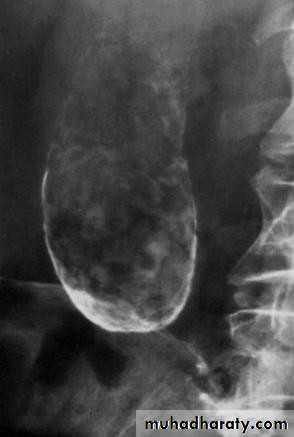

• MRCP

• Magnetic resonance cholangio- pancreatography crosssectional

• image demonstrating a hilar mass (thick• arrow) and gallstones (thin arrow)